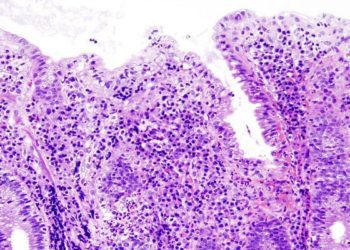

Vedolizumab as Induction and Maintenance Therapy for Ulcerative Colitis

Vedolizumab is a humanized monoclonal antibody targeting α4β7 integrin, which modulates gut lymphocyte trafficking and has shown efficacy for symptomatic relief in ulcerative colitis and Crohn’s disease in smaller phase II trials. Although similar in target to natalizumab (Tysabri), which antagonizes α4β1 and α4β7 integrin interactions to modulate CNS lymphocyte trafficking and has been used to treat MS, vedolizumab is reputed to have more gut specificity and avoid the limiting side effects of PML by JC polymoavirus reactivation. In these two phase 3 randomized, double blinded, placebo control trials, patients with active ulcerative colitis and Crohn’s disease were randomized to vedolizumab or placebo induction and maintenance therapy. In the ulcerative colitis induction trials, there was a statistically significant difference in clinical response (47.1% vs. 25.5%, p < 0.001) and a greater proportion of patients receiving vedolizumab had clinical remission (16.9% vs. 5.4%, p = 0.001). Similarly, for Crohn’s diease patients, there was a greater proportion of clinical remission at 6 weeks (14.5% vs. 6.8%, p = 0.02). For the ulcerative colitis maintenance trials, at one year there was a greater proportion of clinical remission in patients recieiving vedolizumab every 8 weeks and 4 weeks compared to placebo (41.8% vs. 44.8% vs. 15.9%, p < 0.001 for both comparisons). Results were similar for Crohn’s disease patients (39.0% for q8weeks, 36.4% for q4weeks, 21.6% for placebo, p < 0.001 and p = 0.004 respectively). No cases of PML were found in either study, however there were more serioud adverse events for Crohn’s disease patients receiving vedolizumab. Vedolimuzab potentially be an efficacious addition to the compendium of pharmacologic treatments for ulcerative colitis and Crohn’s disease.